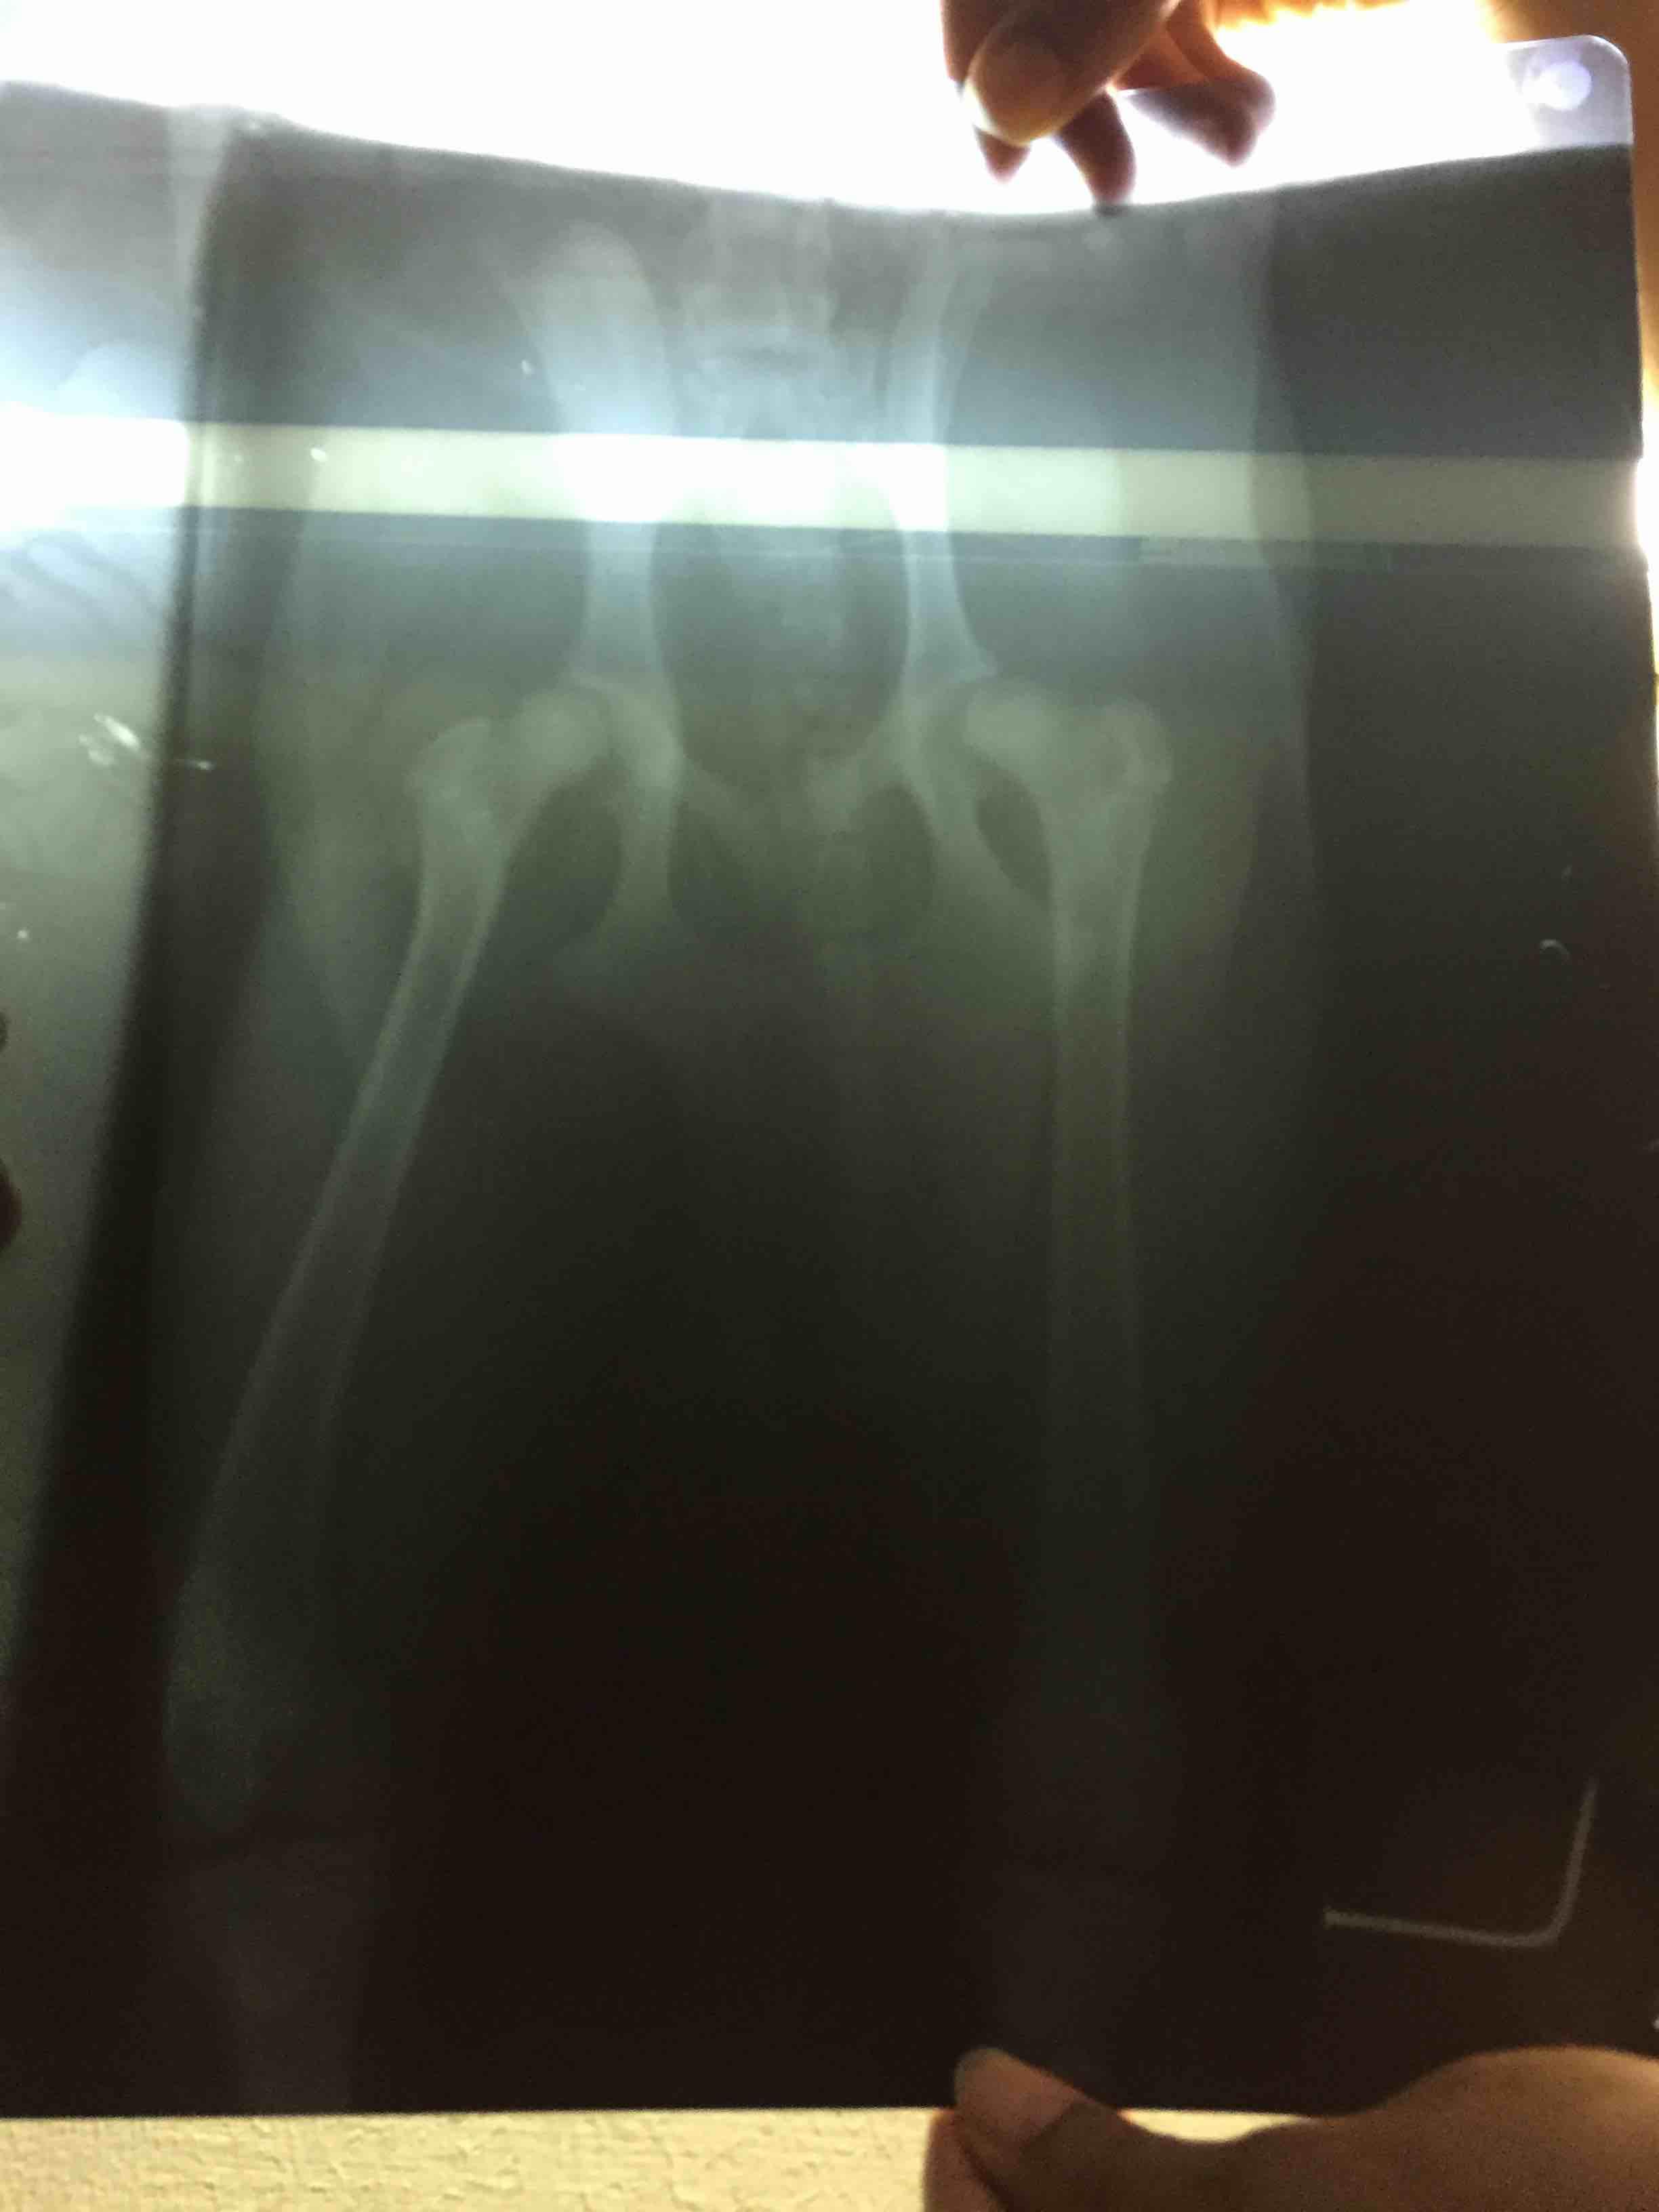

Question - Are my pet's hind legs, back & joints normal? Need to understand what his X-Ray means. Issue - My pet cries before getting up. This is happening since 15-20 days now. Also, he takes quite sometime to get up. Attaching his hind legs X-Ray Thank you

These xrays are not good enough quality and the positioning of the limbs is not good either, it will be very difficult to determine if there is a problem according to those xrays. i personally cannot see anything abnormal but you may want to have it sent to an xray specialist.